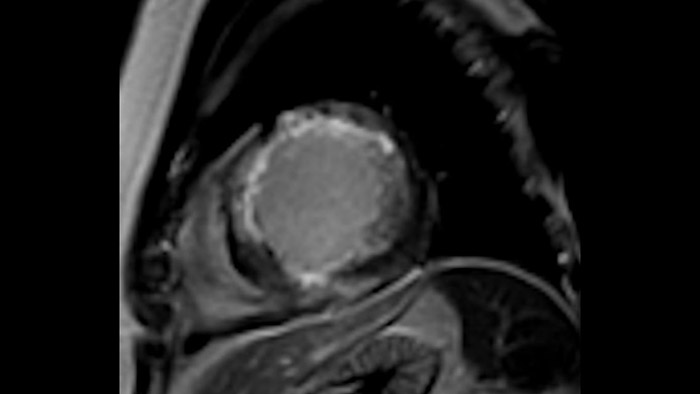

Comprehensive cardiac MR imaging

Diagnostic and prognostic utility of cardiac MR is increasing. Assess the anatomy and function of the heart using cine acquisitions, acquire information about perfusion and viability of the cardiac tissue, visualise potential edema with black blood sequence, access and even quantify tissue characterisation with CardiacQuant.